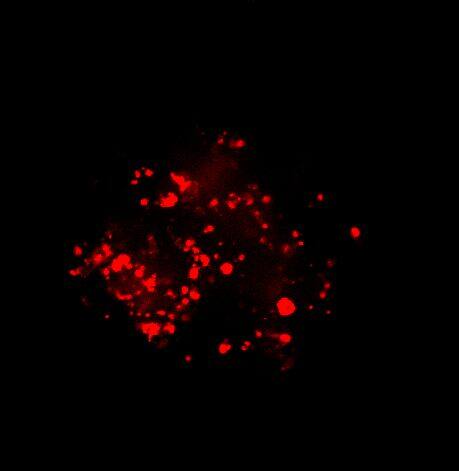

为了生成 3D 球体,将 NCI-H460 细胞(源自非小细胞肺癌)以两种不同的密度接种在超低吸附培养板中:3×103 个细胞/孔或 700 个细胞/孔。在直径分别达到约 400-500 或 150-200 um 后,用细胞毒素剂处理球体 6 天。通过使用钙黄绿素 AM 和碘化丙啶 (PI) 的活/死染色来观察和评估药物的效果。钙黄绿素 AM 是一种细胞渗透性染料,用于测定细胞活性。非荧光钙黄绿素 AM 在活细胞中被细胞内酯酶水解后转化为(绿色)荧光钙黄绿素。PI 是一种红色荧光核染色剂,通常用于检测死亡细胞,因为它不能进入完整的活细胞。最后,使用 Hoechst 染料将细胞核染成蓝色。

我们采用 CrestOptics X-Light V3 转盘共聚焦结合 Prime BSI 相机(Photometrics,像素尺寸 6.5 um)进行采集。我们比较了使用 20 倍空气物镜(CFI Plan Apo Lambda,尼康,0.7 NA 和 1mm WD)和 25 倍硅油物镜(CFI Plan Apo Lambda S,尼康,1.05 NA 和 0.55 mm WD)进行的采集。在图 A 中,我们展示了从总共 150 um 的 Z 堆栈中获得的最大强度投影 (MIP) 图像;特别是,使用 20 倍空气物镜和 25 倍硅油物镜获得了相同的球体。图 B 显示了使用两种物镜获得的 3D 球体同一区域的放大。

图 A:使用 20 倍空气物镜(顶部)和 25 倍硅油物镜(底部)获得的肿瘤球体 Z 堆栈的最大密度投影 (MIP)。活细胞用钙黄绿素(绿色)标记,死细胞用 PI(红色)标记。细胞核用 Hoechst(蓝色)染色。比例尺:100 um。这些图像是使用 CrestOptics X-Light V3 转盘获取的。

图 B:使用 20 倍空气物镜(左)和 25 倍硅胶物镜(右)获得的 3D 球体同一区域的放大。活细胞用钙黄绿素(绿色)标记,死细胞用 PI(红色)标记。细胞核用 Hoechst(蓝色)染色。这些图像是使用 CrestOptics X-Light V3 转盘获取的。